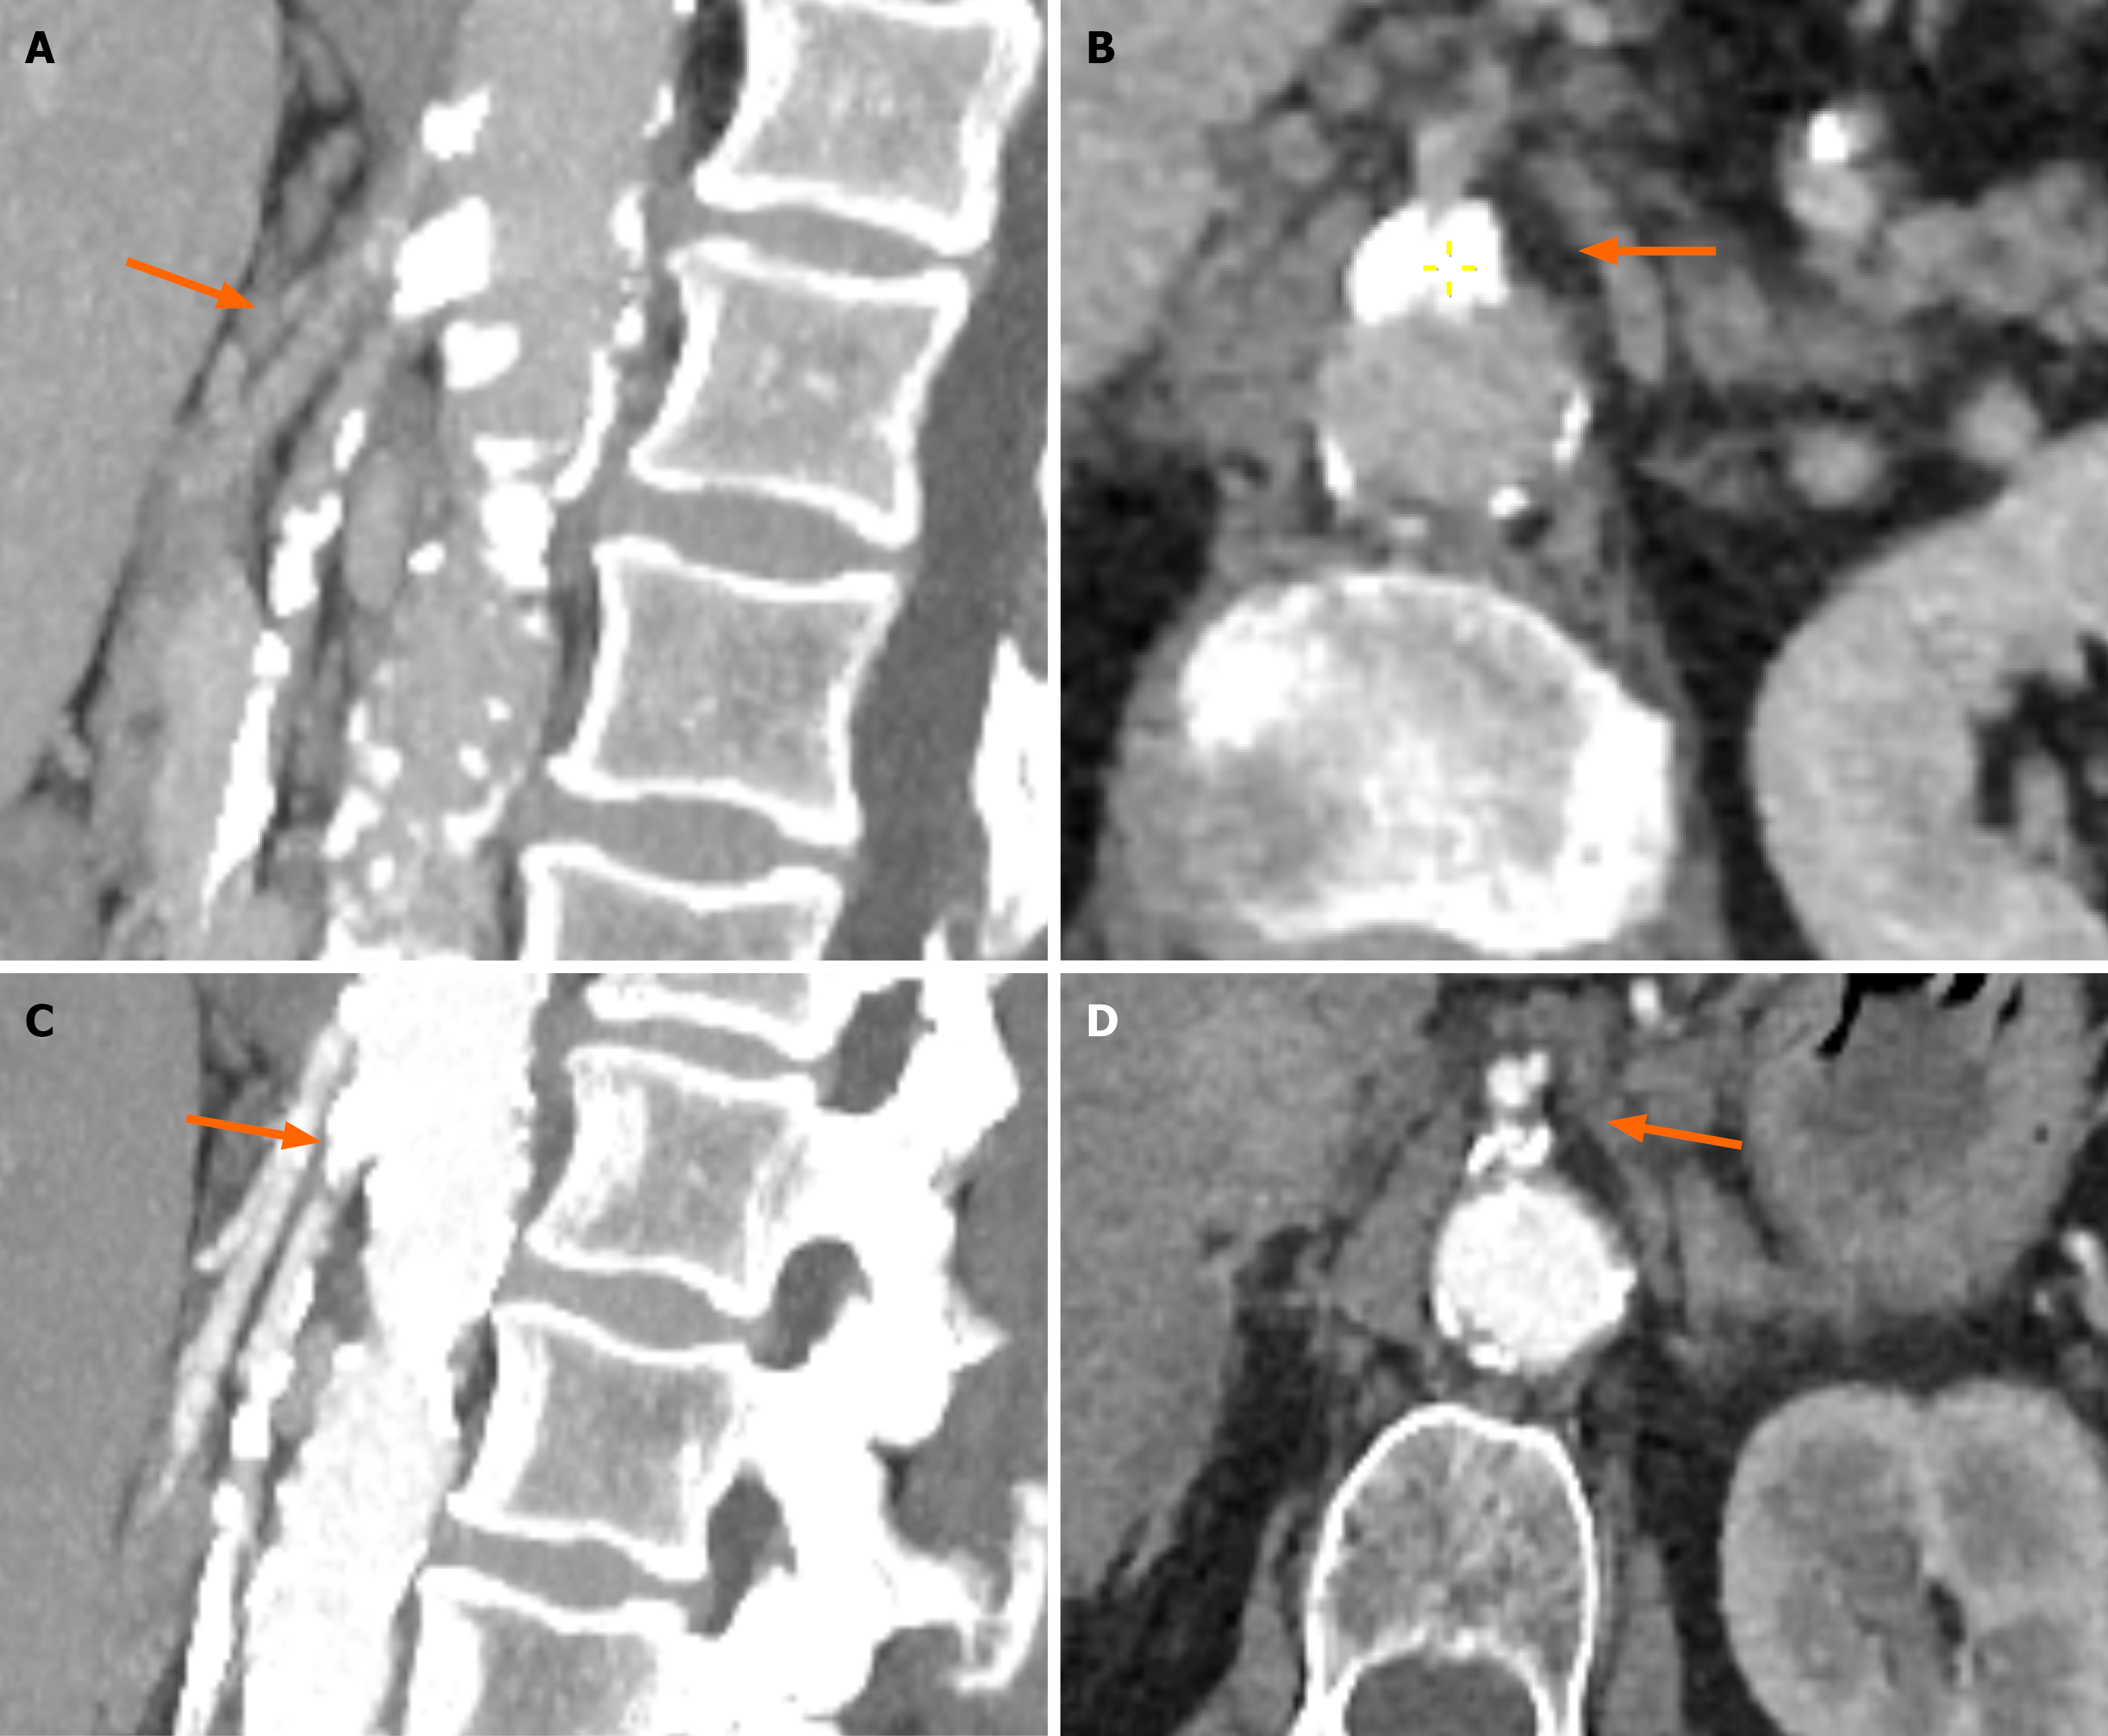

Case 1: The gastroenterology registrar re-reviewed the prior abdominal CT, which had been performed months earlier as part of the initial work-up for non-specific abdominal pain. This review revealed extensive calcifications at the origins of the superior mesenteric artery (SMA) and celiac trunk (Figure 1A and B), which had not been reported in the original radiology interpretation. CT angiography was then performed to assess the mesenteric vasculature, confirming high-grade stenosis of the SMA with suspected 1.5 cm portion of the vessel showing occlusion (Figure 1C and D). Figure 1A and B (CT abdomen protocol) show the presence of significant calcification at both the celiac trunk and SMA (Figure 1A, sagittal reconstruction), with extensive calcification at the SMA ostium when viewed in axial view. Figure 1C and D (CT angiography protocol) show extensive calcifications at both the celiac trunk and SMA, with a 1.5 cm portion of the SMA distal to the calcification showing vascular occlusion (Figure 1C, sagittal reconstruction). Figure 1D shows extensive calcification at the SMA ostium when viewed in axial view. Given the patient’s prior history of GCA, a review of the patient by a rheumatologist, alongside a positron emission tomography (PET-CT) were done to assess for the presence of clinical and/or tomographic signs of reactivation of underlying GCA. The PET-CT and the clinical exam were both negative for GCA reactivation.